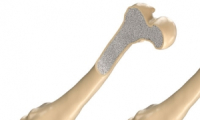

توصل باحثون إلى آلية بيولوجية مهمة تتحكم في قوة العظام وكثافتها، ما قد يفتح الباب مستقبلاً لتطوير علاجات قادرة على استعادة قوة العظام لدى مرضى هشاشة العظام، وهو مرض يصيب ملايين الأشخاص حول العالم.